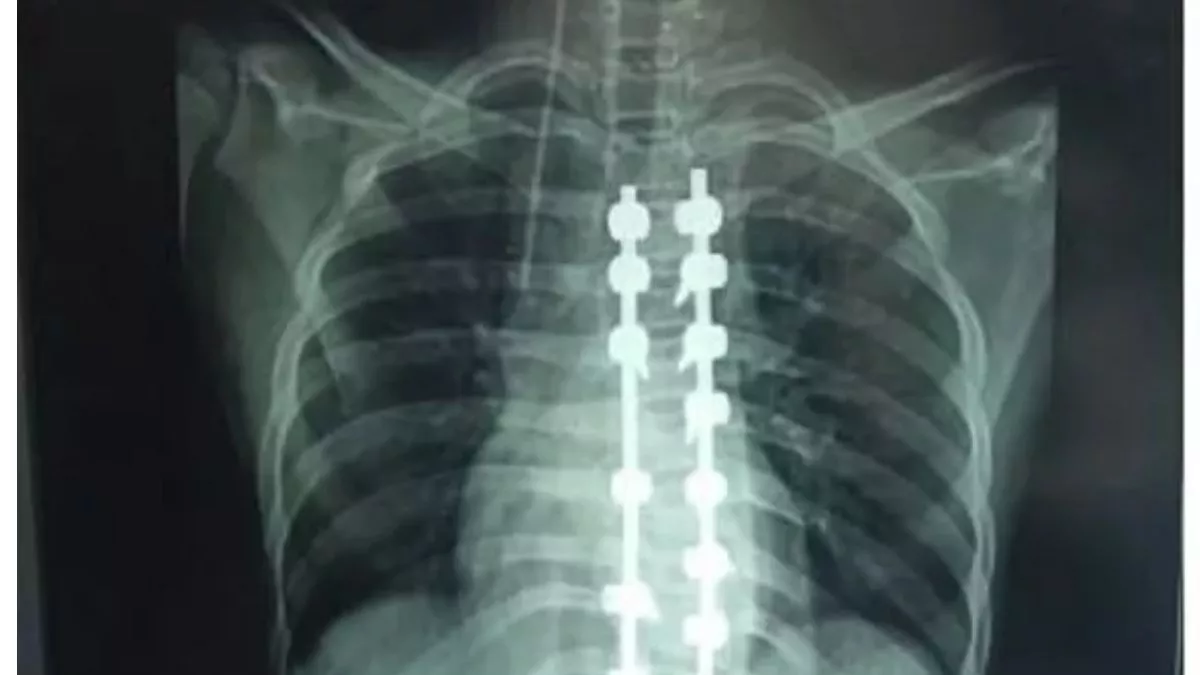

प्रयागराज, दुर्घटना अथवा अन्य कारणों से जिनकी हड्डियां टूट जाती हैं और इलाज में रिंग फिक्सेटर या लिंब रिकन्सट्रक्शन डिवाइस का इस्तेमाल किया जाता है, उन्हें जांच के लिए अब बार-बार एक्सरे कराने की जरूरत नहीं पड़ेगी। सेंसर बता देगा कि हड्डी कितनी जुड़ गई है।

मोतीलाल नेहरू राष्ट्रीय प्रौद्योगिकी संस्थान (एमएनएनआईटी), प्रयागराज और किंग जॉर्ज मेडिकल यूनिवर्सिटी (केजीएमयू), लखनऊ के विज्ञानियों ने मिलकर इसके लिए एक अत्याधुनिक सेंसिंग डिवाइस विकसित की है। इससे एक्सरे पर होने वाले खर्च के साथ ही रेडिएशन के दुष्प्रभावों से भी राहत मिलेगी। इस डिवाइस का परीक्षण प्रयोगशाला स्तर पर सफलतापूर्वक पूरा कर लिया गया है। अब इसे मरीजों पर आजमाने की तैयारी की जा रही है। शोधकर्ताओं ने डिवाइस के पेटेंट के लिए आवेदन भी कर दिया है।

सर्जरी के समय ही यह सेंसर हड्डी जोड़ने वाली रॉड या फिक्सेटर पर लगाया जाएगा, जो समय-समय पर यह जानकारी देगा कि हड्डी की स्थिति क्या है। यह सेंसर ऑप्टिकल फाइबर तकनीक पर आधारित है, जो पूरी तरह से इलेक्ट्रिकल रूप से निष्क्रिय होता है और शरीर में किसी भी प्रकार की प्रतिक्रिया नहीं करता। इस सेंसर की सबसे खास बात यह है कि इसे कृत्रिम बुद्धिमत्ता (एआई) और रियल टाइम डेटा ट्रांसमिशन से सुसज्जित किया गया है। यानी डाक्टर को किसी भी समय, कहीं से भी मरीज की हड्डी जुड़ने की सटीक जानकारी प्राप्त हो सकेगी। इससे मरीज को बार-बार अस्पताल जाने की आवश्यकता भी नहीं होगी।

मुख्य अनुसंधानकर्ता डाॅ. अभिषेक तिवारी ने बताया कि लगभग दो वर्षों के प्रयास के बाद सेंसिंग डिवाइस को प्रयोगशाला स्तर पर विकसित कर उसका परीक्षण भी सफलतापूर्वक पूरा किया जा चुका है। अब इसे केजीएमयू के सहयोग से क्लीनिकल ट्रायल के चरण में लाया जा रहा है, जहां वास्तविक मरीजों पर इसका परीक्षण किया जाएगा। सेंसर डॉक्टर को यह बताने में मदद करेगा कि फिक्सेटर कब हटाना है और कब नहीं।